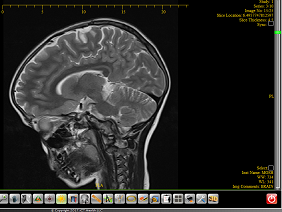

The Department of Neurosurgery has a long-standing reputation for being a national and international leader in the surgical treatment of patients with brain tumors and skull base tumors, and our neurosurgeons are known for their ability to handle the most complex cases, including skull base lesions and tumors in eloquent brain areas. We utilize the most sophisticated, state-of-the-art technologies, including frameless stereotactic systems, advanced functional mapping and neuro-navigation techniques, equipment for transnasal and transventricular endoscopic approaches.

We perform the surgical removal by minimally invasive technique like Endoscopy for pituitary or intraventricular tumors or by Microsurgery for massive brain tumors. We are nearly always guided by the Neuronavigation.

Neuronavigation